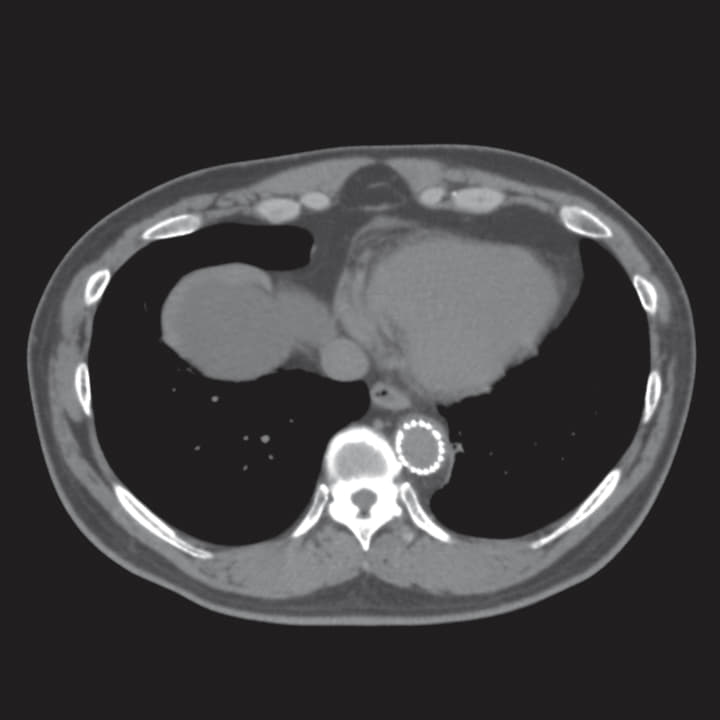

若年者の慢性B型解離に対するTEVARで、比較的急峻な大動脈弓部形態を有している。遠位弓部にあるエントリーを閉鎖するため、急峻な大動脈弓部の頂点をやや越えた位置に中枢端を配置する必要があり、大弯側は中枢パーシャルアンカバーステントの頸部分枝入口部への侵入、小弯側ではbird beakの発生に最大限の注意が必要だが、この急峻な解剖に対しアクティブコントロールシステムが有用であった。

エントリーはT5レベルにあり大きさは29 mm、Zone 3大弯側の解離腔には比較的厚い(13 mm)偽腔内の血栓を認めたため、Zone 2ランディング+デブランチ(Ax-Axバイパス)の方針とした。

ここからは術者がシースの固定とデリバリーカテーテルの操作を行い、助手がデリバリーしたデバイスの位置調整のためのガイドワイヤーの大弯側への押しつけと保持を行う共同操作で展開手技を行った。続いてTGMR343420Jを適正位置まで進行させた。DSAを行い左総頸動脈(LCCA)及び左鎖骨下動脈(LSA)の位置および大動脈の形状を確認した。ガイドワイヤ一を適度に押し、デバイスが大弯側に押し当てられていることを確認し、Zone 2にパーシャルアンカバーステント先端が位置するようにして一次展開を行った。デリバリーカテーテルを確実に保持することでマイグレーションを予防しつつアンギュレーションコントロールダイヤルをゆっくり回転させ、大動脈弯曲とデバイスの弯曲がフィットするよう調整した。完全展開後、 デバイス小弯側と弓部小弯側がパラレルになるようアンギュレーションコントロールダイヤルをゆっくり回転させた。

若年症例では弓部の形状が急峻である。弓部の頂点をやや越えた位置にステントグラフト中枢端を留置する場合は、従来のステントグラフトではデバイス自体が直線化し、大弯側において頸部分枝内にベアステントが侵入することによりRTADの原因となることが懸念される。また、小弯側ではいわゆるbird beakの発生によるエンドリークが危惧される。本症例では、アンギュレーションコントロールを用いることにより本来の弓部の形状にデバイスを追従させることに成功した。さらに、アクティブコントロールシステムでは、一次展開、完全展開の2段階操作による展開が可能であるため、ステントグラフトの中間径まで一次展開を行った後に血流による影響を抑えつつ留置位置の微調整を行うことができ、最終留置位置の予想がつきやすく正確なデバイス留置が可能であった。また、慢性早期のTEVARは良好なリモデリングを確認することができた。